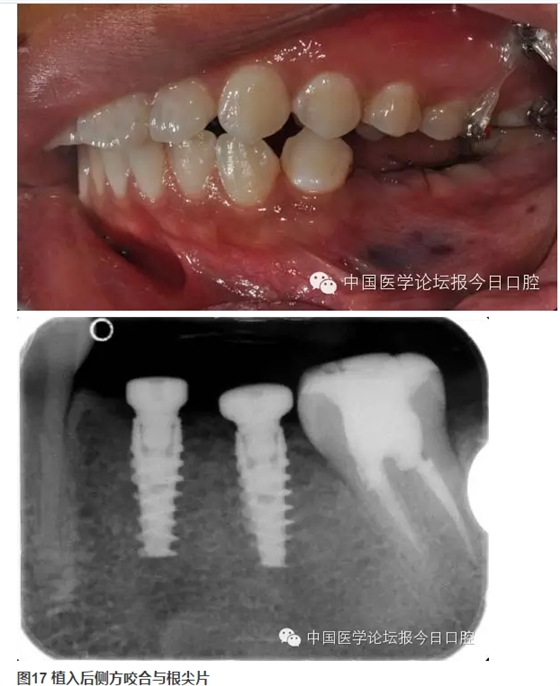

牙周情況尚可,有少量牙結(jié)石,牙齦無(wú)明顯紅腫。35、36 缺失,25、26 過(guò)長(zhǎng),17 與47,27與37正鎖牙合,咬合時(shí)26、27 的牙尖頂?shù)綄?duì)頜缺牙區(qū)牙槽嵴黏膜上。37、47死髓牙。

全口曲面體層片顯示:35、36缺失,缺牙區(qū)牙槽骨有足夠的骨高度,47未行根管治療,38、48近中阻生,18殘根,28頰面深齲近髓。